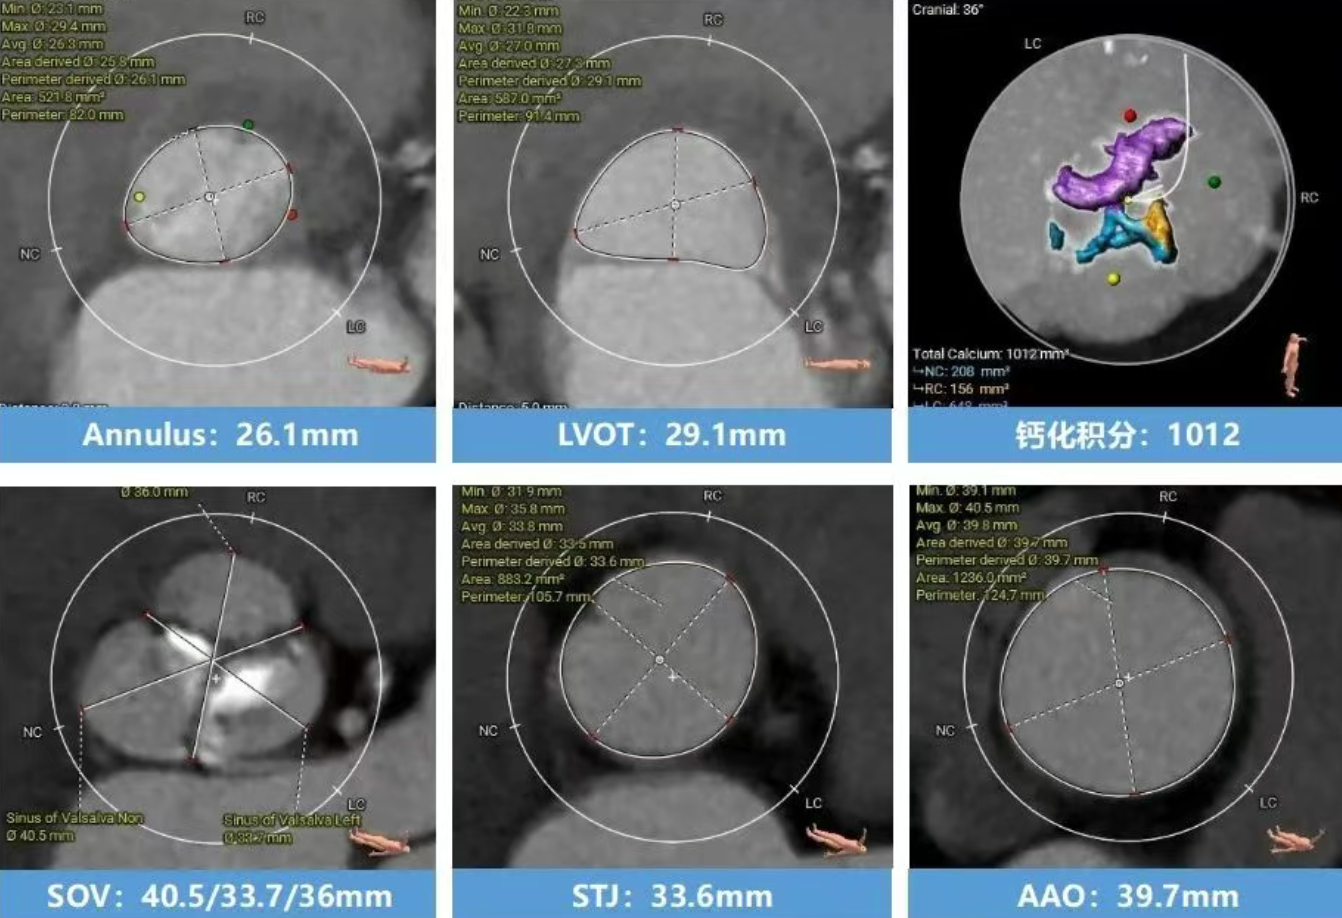

术前CT分析(76岁,女性)

▶ Type1型二叶式主动脉瓣(L-R),瓣叶增厚,重度钙化,钙化分布不均匀,无窦钙化延申至STJ以上,LVOT偏直筒型。

▶ 左右冠脉开口高度尚可,左窦瓣叶切线测量距离>冠脉开口下缘到根部距离。

▶ 心室腔内径尚可,心室壁厚度可,心尖尚可。

▶ 瓣环水平夹角72°,横位心,主动脉弓角、弓距尚可。

主动脉根部测量

瓣上结构测量